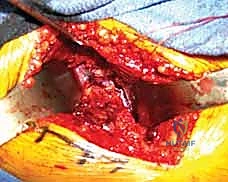

يقوم الأستاذ الدكتور محمد هطيف بإجراء هذه العمليات المعقدة في أفضل مستشفيات صنعاء المجهزة بغرف عمليات حديثة (بتقنية تدفق الهواء الصفائحي Laminar Airflow لتقليل العدوى).

1. الرد المغلق العاجل (Urgent Closed Reduction)

بمجرد وصول المريض للطوارئ، وفي حال وجود خلع مصاحب للكسر، يقوم الدكتور هطيف أو فريقه برد المفصل المخلوع يدوياً تحت التخدير العام في أسرع وقت ممكن (يفضل خلال 6 ساعات من الحادث) لتقليل الضغط على الأوعية الدموية وحماية الشريان الفخذي المنعطف الإنسي.

* في الحالات المعقدة (Pipkin IV)، قد يستخدم تقنية الخلع الجراحي الآمن للورك (Ganz Surgical Dislocation)، وهي تقنية متقدمة جداً تتيح خلع المفصل جراحياً بشكل آمن تماماً، وإصلاح الكسر من جميع الجهات، ثم إعادته، وهي تقنية لا يتقنها سوى كبار جراحي العظام في العالم.